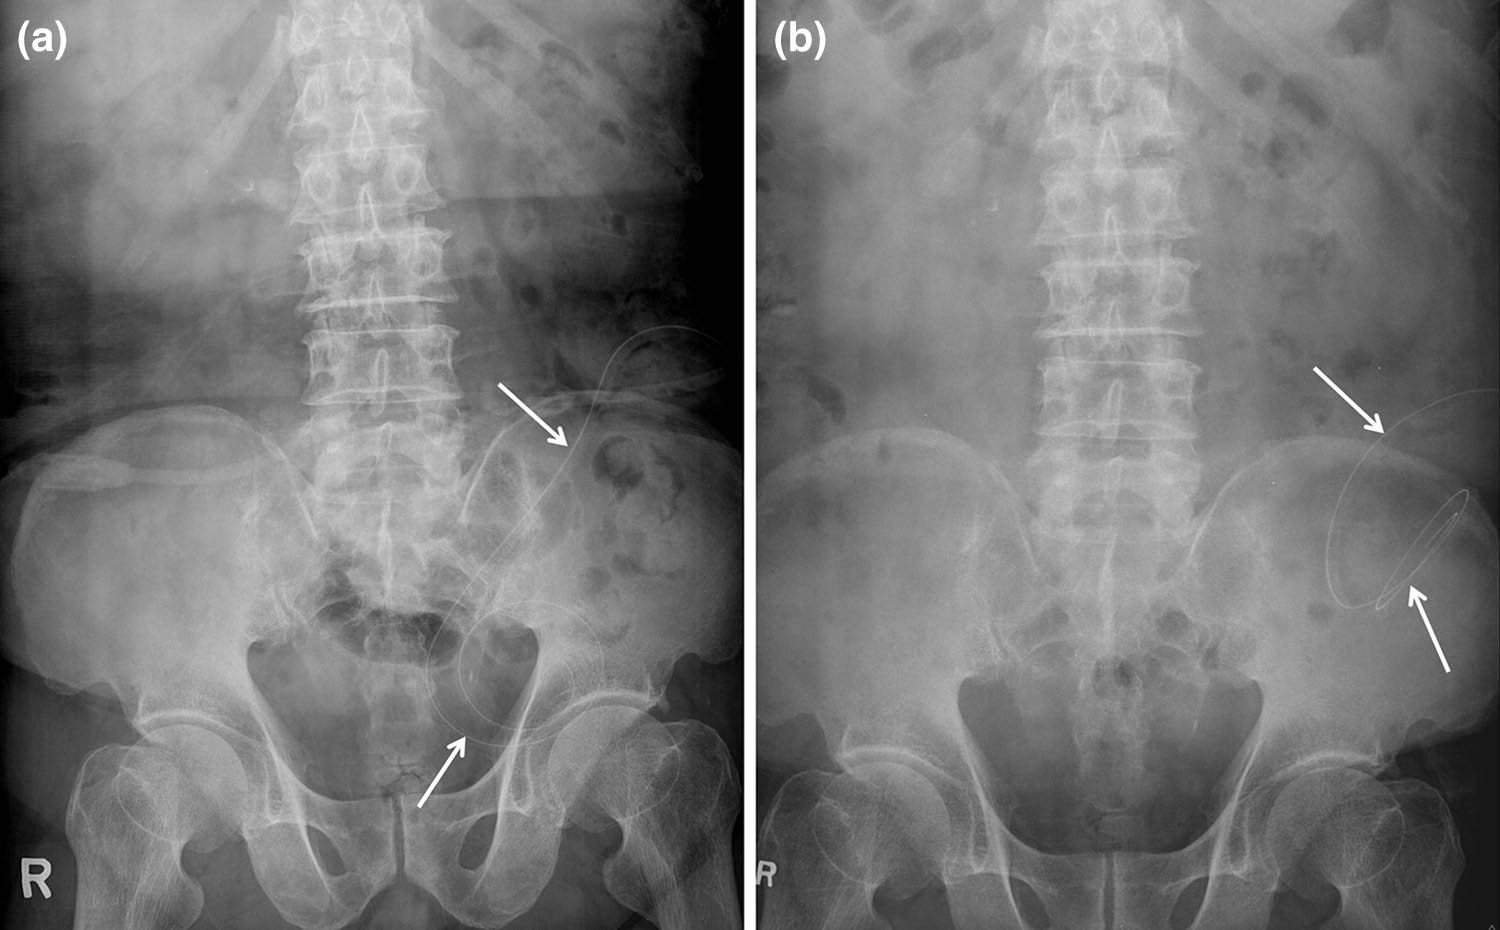

宫内节育器

宫内节育器(IUDs)是常用且高效的临时避孕装置,应位于子宫内膜腔中央。然而,它们可能在子宫腔内移位,远端脱入阴道,或通过子宫穿孔进入腹腔(图10)[2]。